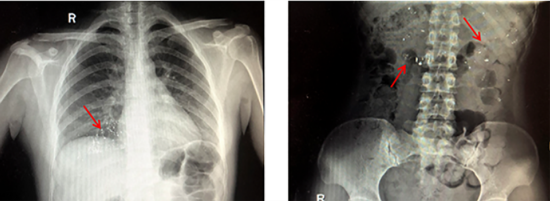

医生检查后发现,孩子的口腔內并没有玻璃碎片,拍片子后也发现孩子其实并无大碍,就问孩子的父母是否做过什么急救措施。孩子的父亲就说了,自己发现孩子咬破水银后,二话没说,首先就是清理了孩子的口腔,将玻璃碎片都取了出来,然后找了一个密封的瓶子把水银都密封了起来。这时,父亲发现孩子的口腔粘膜完好无损,也松了一口气。紧接着父亲让孩子喝了一盒牛奶。